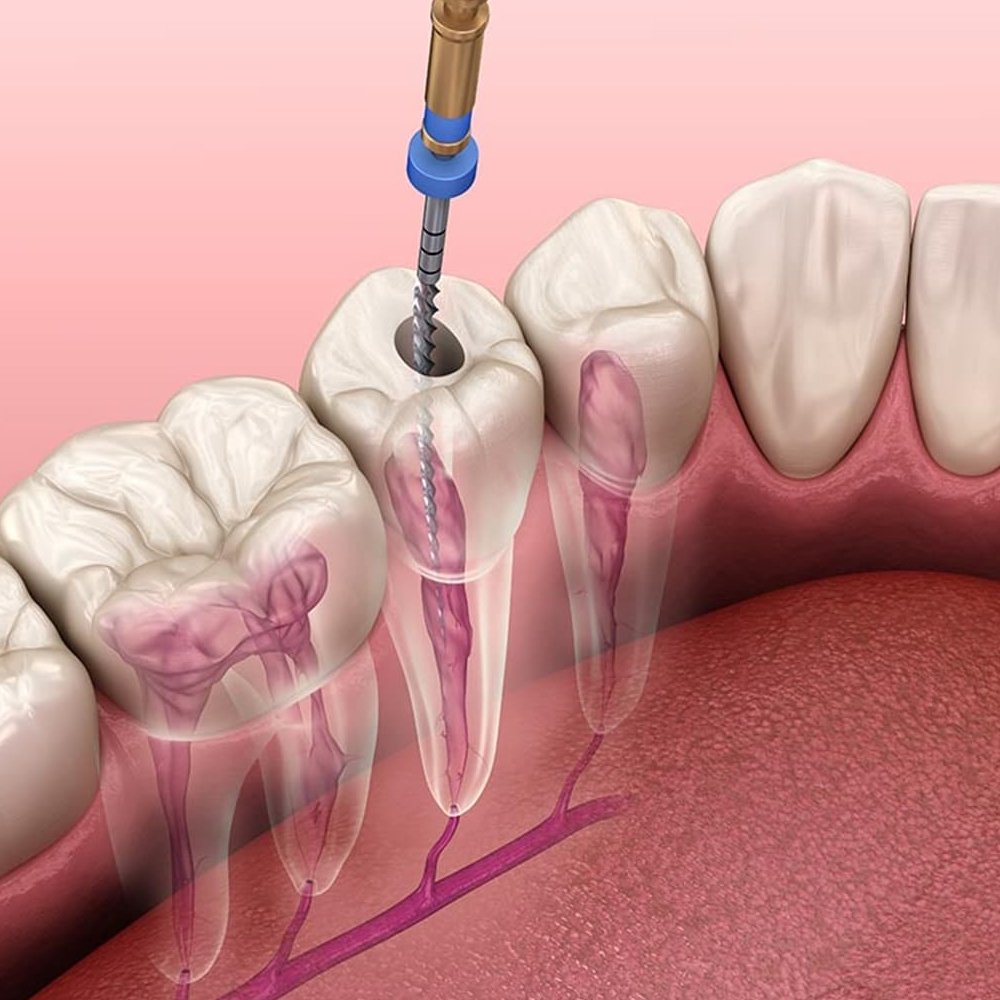

Kanal Tedavisi (Endodonti)

Dişin içindeki pulpa (sinir, damar paketi) iltihaplandığında veya enfekte olduğunda uygulanır. Bu tedavi ile dişin çekilmesine gerek kalmadan ağızda tutulması sağlanır.

6) Kanal tedavisi sonrası dişim zayıflar mı?

Pulpa çıkarıldığından kırılganlık artabilir; uygun onlay/kronla desteklenirse uzun yıllar işlev görür. Mikroskobik çalışma sızıntı riskini azaltır.

Kanal tedavisi başarısız olursa? Retreatment veya apikal cerrahi seçenekleri vardır.